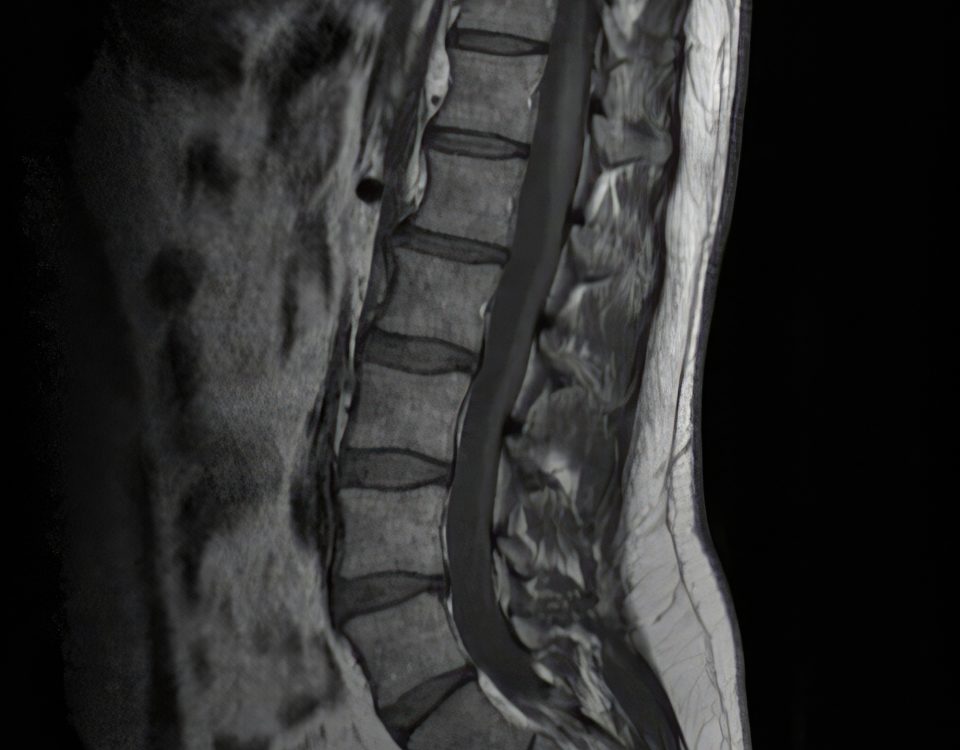

La catégorie « Chirurgie lombaire » regroupe l’ensemble de nos articles et pages dédiés aux pathologies et aux traitements chirurgicaux du bas du dos. Vous y trouverez des informations claires sur les affections courantes (hernie discale, arthrose facettaire, sténose lombaire, spondylolisthésis, fractures, discopathies), les différentes techniques opératoires disponibles (microchirurgie, endoscopie, fusion lombaire, prothèse discale, stabilisation dynamique), leurs indications respectives, le déroulement des interventions et les étapes de la récupération. Cette section a pour objectif d’accompagner chaque patient dans sa compréhension des options de chirurgie lombaire, qu’il s’agisse de soulager la douleur, de restaurer la mobilité ou de traiter une instabilité, en présentant les innovations les plus récentes et les conseils pour optimiser le retour à la vie active.

- MRI